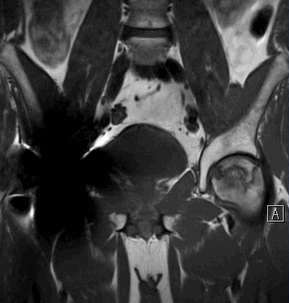

Рисунок 3. МРТ тазобедренных суставов

Состояние после протезирования правого тазобедренного сустава.

На фоне минимального отека костного мозга в области опорного сегмента головки бедренной кости слева субхондрально определяется зона остеонекроза с четкими неровными «географическими» контурами, отделенная от неизмененных участков кости ободком (грануляционная ткань). Головка бедренной кости не деформирована, без признаков субхондрального импрессионного перелома.

Рисунки 4,5. МРТ тазобедренных суставов

На фоне умеренного отека костного мозга по суставной поверхности головки бедренной кости (преимущественно в наружных отделах) субхондрально определяется зона остеонекроза с четкими неровными «географическими» контурами, отделенная от неизмененных участков кости ободком (грануляционная ткань). Головка бедренной кости в передне-верхних отделах деформирована за счет формирования импрессионного субхондрального перелома.